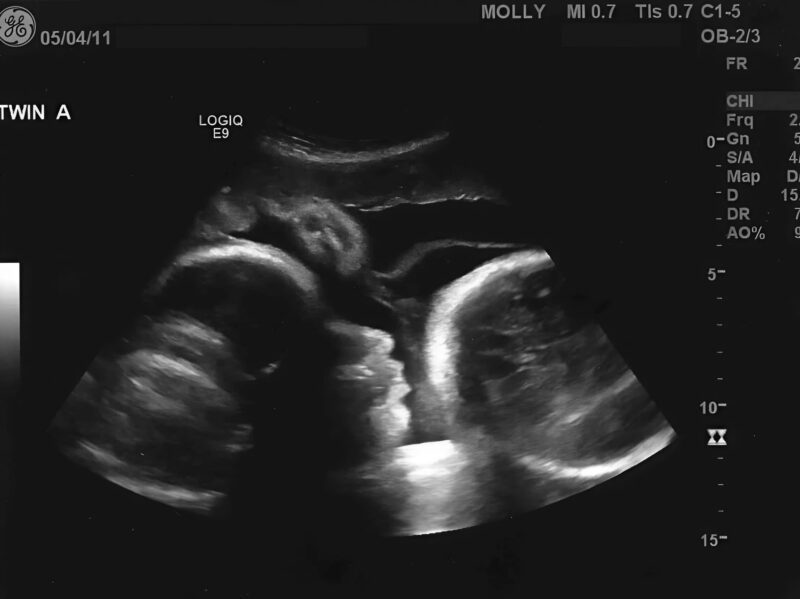

Όταν, «σύμφωνα με τους υπολογισμούς της», μπήκε στον ένατο μήνα, η Λαρίσα αποφάσισε επιτέλους να κλείσει ραντεβού με τον γυναικολόγο για να μάθει πώς θα εξελιχθεί ο τοκετός. Ο γυναικολόγος ανησύχησε ήδη βλέποντας την ηλικία της στο φάκελο. Αλλά όταν άρχισε την εξέταση, το πρόσωπό του ασπρισε αμέσως με αυτό που είδε στην οθόνη 😨😱

— Ο «γαστρεντερολόγος» σας έκανε λάθος. Το τεστ ήταν ψευδώς θετικό. Μέσα σας… υπάρχει ένας τεράστιος όγκος.

— Κυρία μου, έχετε όγκο στην ωοθήκη, στο μέγεθος ενός τελειόμηνου μωρού. Αυτός μεγάλωνε όλους αυτούς τους μήνες. Αυτός σας έκανε να νιώθετε «κινήσεις». Και αυτός είναι η αιτία του πόνου. Ο όγκος έχει ήδη κάνει μεταστάσεις. Η κατάσταση είναι κρίσιμη. Χρειάζεστε άμεση επέμβαση, χημειοθεραπεία… και έχουμε πολύ λίγο χρόνο.